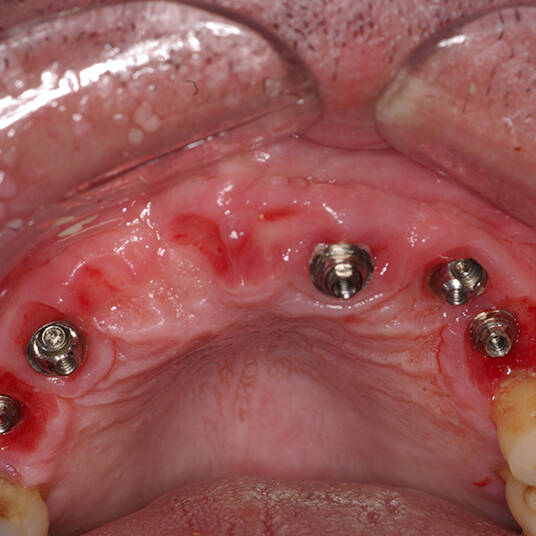

Na Clínica Pontes Odontologia, somos referência em implantes dentários em Fortaleza, oferecendo tratamentos de alta qualidade e tecnologia de ponta. Os implantes dentários são estruturas de titânio posicionadas cirurgicamente no osso maxilar ou mandibular para substituir as raízes dos dentes ausentes. Essa técnica permite a fixação de próteses personalizadas, restaurando a função mastigatória, a estética e a autoestima dos nossos pacientes.

Utilizamos a tecnologia CAD CAM, um sistema avançado que possibilita a confecção precisa das próteses dentárias diretamente sobre os implantes. Esse método inovador garante um ajuste perfeito, um resultado estético superior e proporciona muito mais conforto e durabilidade. Com o CAD CAM, nossos pacientes contam com um processo mais rápido e previsível para alcançar o sorriso desejado.